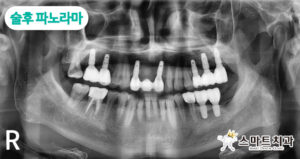

치료 6개월 후 파노라마 사진입니다.

발치 당일 임플란트를 즉시 식립하여 치료를 진행했습니다. 상악 좌측 제2대구치는 뼈가 더 단단한 곳에 식립하기 위하여 위치를 조정했으며, 하악 좌측 제2대구치 본래 자리가 염증으로 인해 뼈가 부족하여 앞쪽으로 식립하였습니다. 임시 틀니를 4개월 정도 착용하고 계셔야 되어서 더욱 정밀하게 제작했는데요, 수술 후 신경치 료도 진행하여 마무리했습니다.